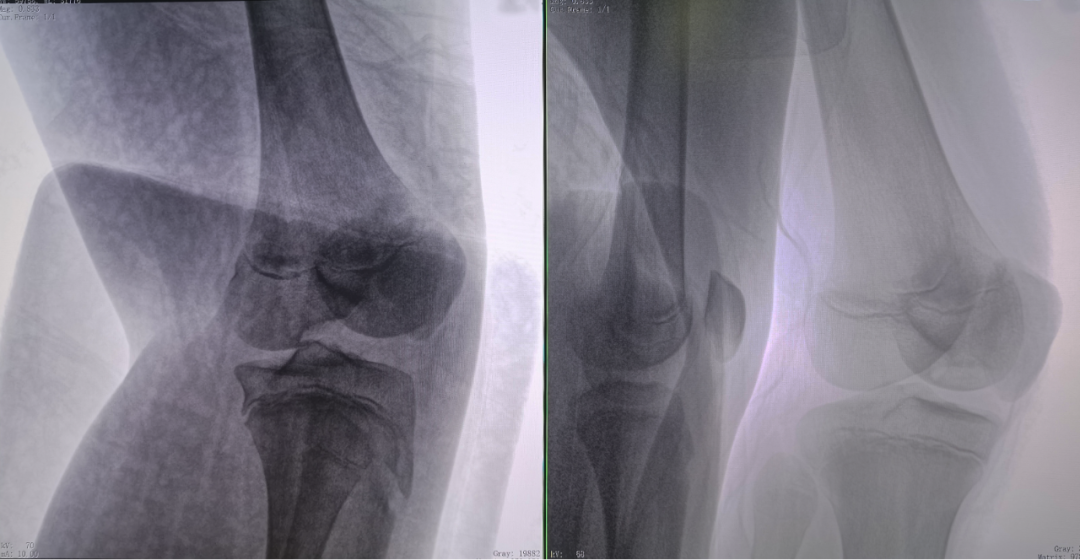

病例2 踝關節骨折復位(31歲)

在踝關節骨折復位手術中,用三維C可以更好地觀察骨折部位的復位情況:

正側位影像觀察脛腓聯合復位良好

從三維影像看,復位欠佳,貼合度不夠